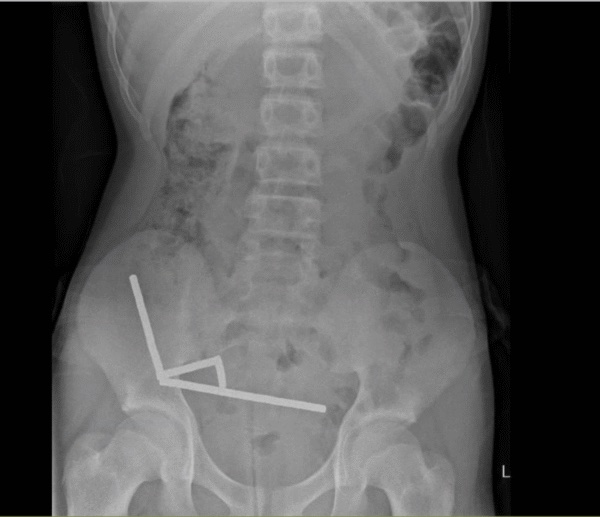

Using an X-ray, doctors imaged four linear chains in separate parts of the boy's bowel.

During surgery, the chains were found in sections of the small bowel and caecum. Squeezing together, they were causing several patches of tissue to die from a lack of blood in what is known as pressure necrosis.